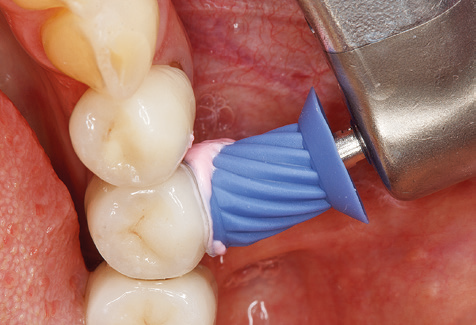

Of course, working tips for the cleaning of implant surfaces are also indispensable for SPT in patients fitted with implants. The implant cleaning attachment on the system used here is characterised by its tapered, hexagonal design. This design allows light, atraumatic penetration of the peri-implant pocket and displays a good cleaning performance (Fig. 7).